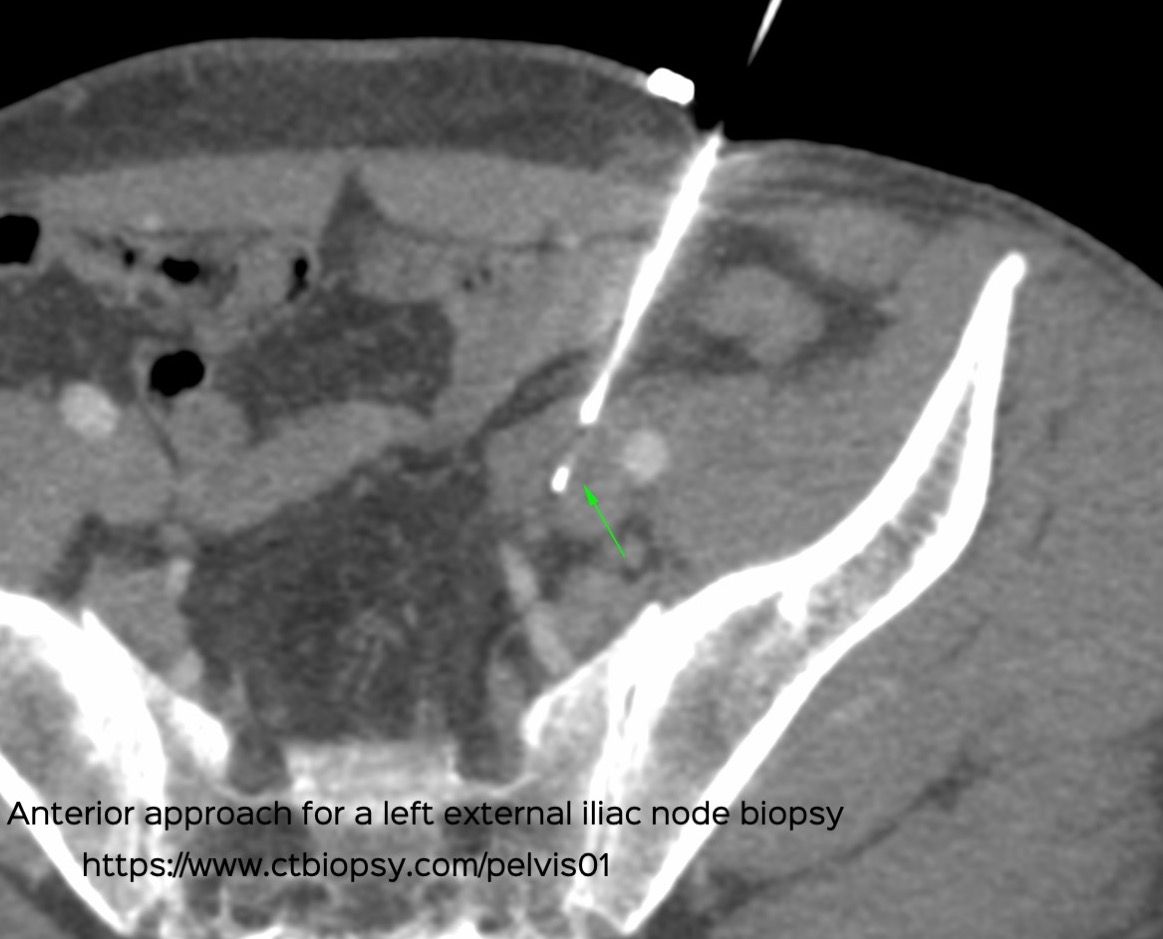

Case 63: Anterior Approach for Iliac Node Biopsy

Bhavin Jankharia - 14 October 2021